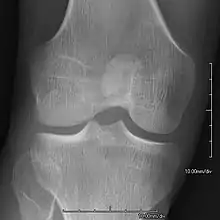

Bones and joints

- Patellar involvement is present in approximately 90% of patients; however, patellar aplasia occurs in only 20%.

- In instances in which the patellae are smaller or luxated, the knees may be unstable.

- Exostoses arising from the posterior aspect of the iliac bones ("iliac horns") are present in as many as 80% of patients; this finding is considered pathognomonic for the syndrome.

An elbow of a man with nail–patella syndrome (NPS)

This is a view from a different angle of the same man's other elbow